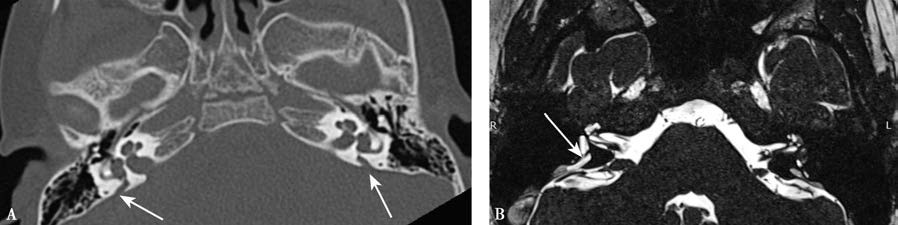

Figure 1 CT and MRI of enlarged vestibular aqueduct

A. Axial CT of the temporal bone, with white arrows indicating bilateral enlargement of the vestibular aqueducts; B. Axial MRI of the temporal bone, with a white arrow indicating enlargement of the right vestibular aqueduct.